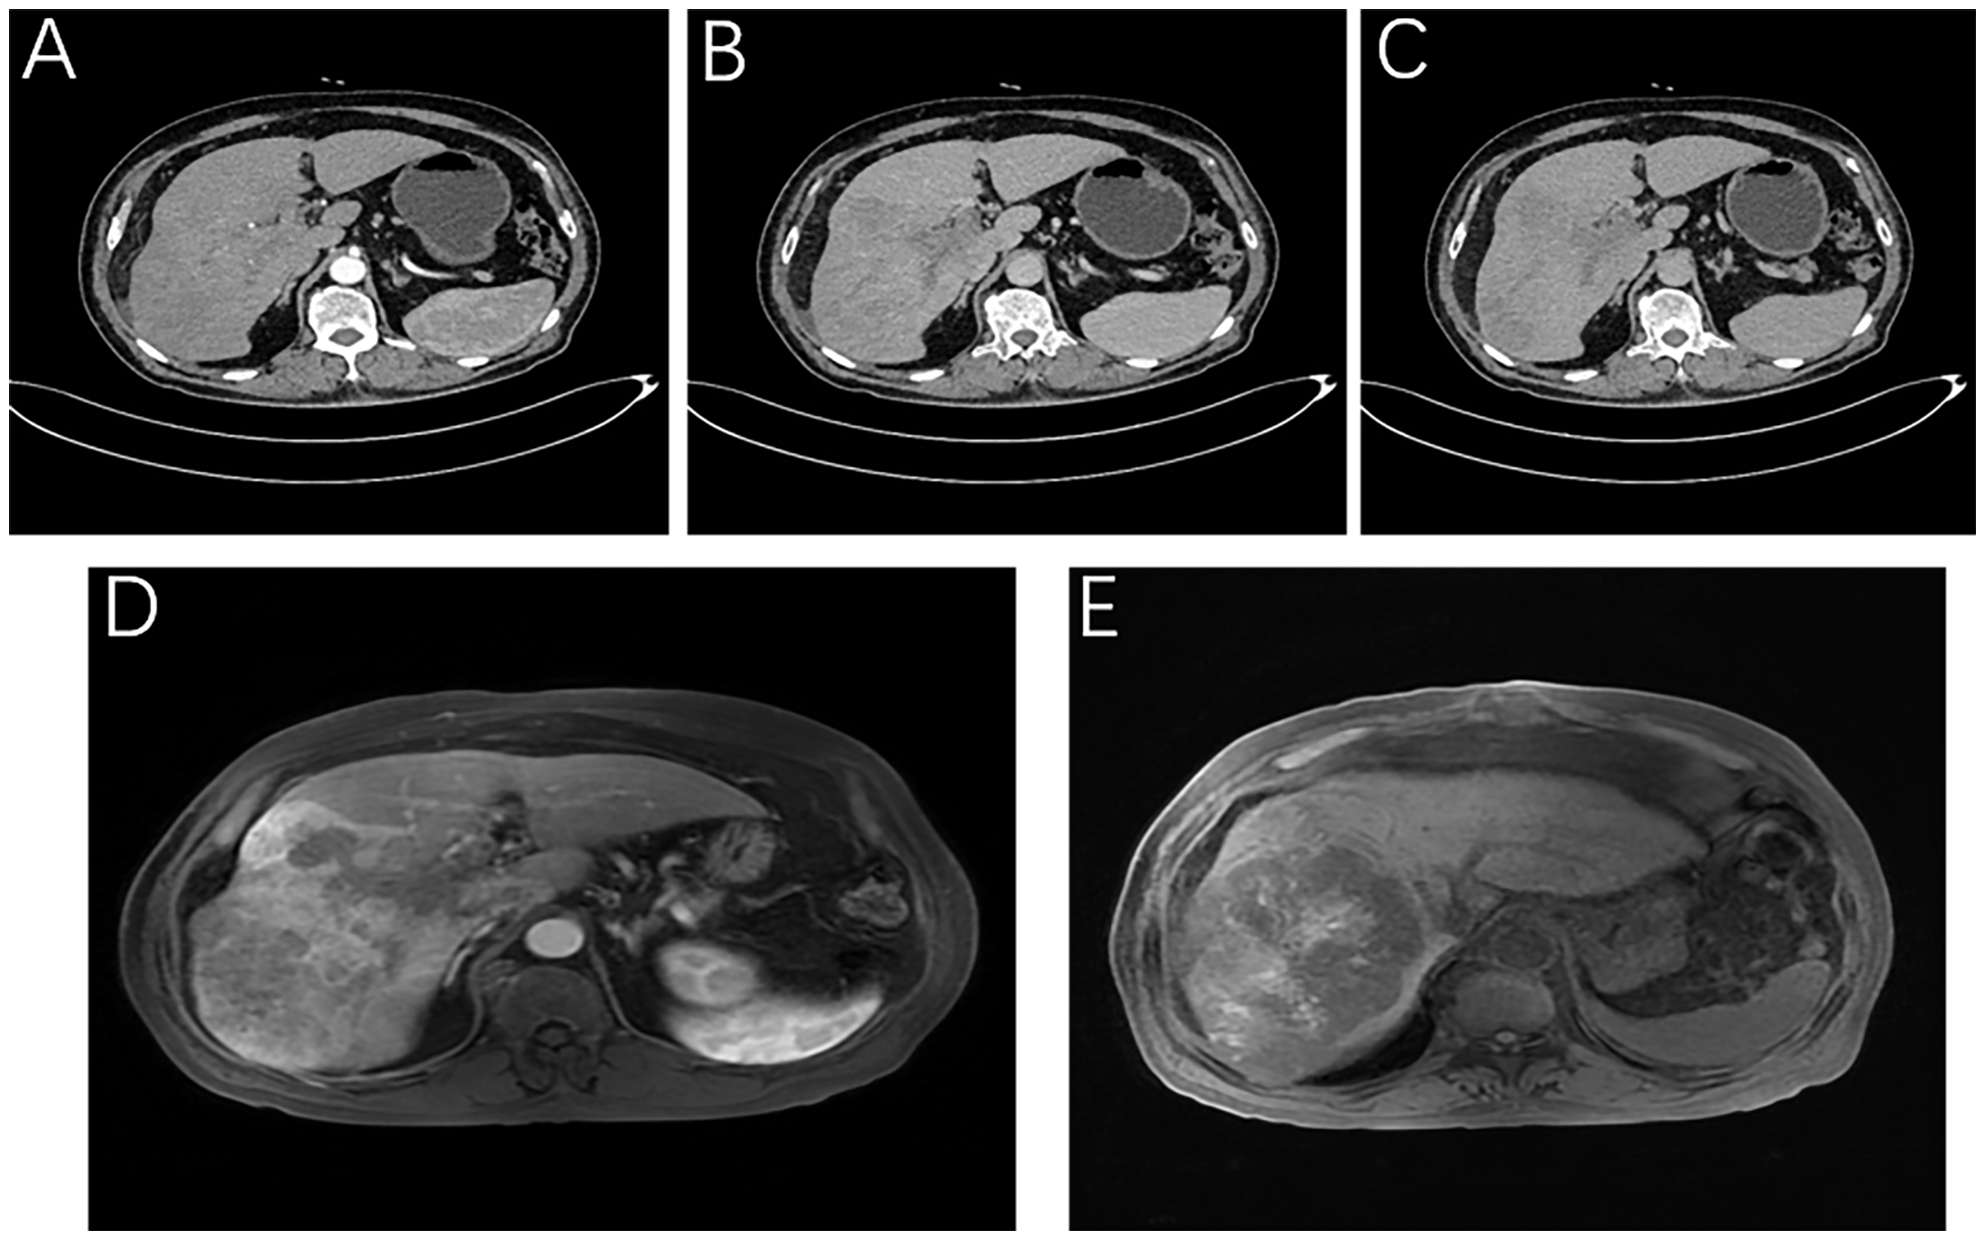

The patient was a 76-year-old male who presented to Lanzhou University First Hospital on August 5, 2021, with upper abdominal bloating and mild pain persisting for over one month. He reported no other symptoms, and an abdominal ultrasound conducted at another local hospital indicated the presence of a liver mass. His medical history included chronic hepatitis B for over 30 years, hypertension, diabetes, and cataract surgery with intraocular lens implantation. Upon physical examination, the patient exhibited normal skin and mucosal color without jaundice, a flat abdomen devoid of abdominal wall varices, and no remarkable gastrointestinal contour or peristalsis. There was no tenderness upon abdominal palpation, and the liver was palpable below the rib margin. Murphy’s sign was negative, and bowel sounds were noted at a rate of four times per minute. Laboratory tests revealed the following values within normal limits: white blood cell count (WBC: 5.03 × 10^9/L), neutrophil ratio (NEUT%: 68.8%), hemoglobin (HGB: 124 g/L), and platelet count (PLT: 205 × 10^9/L). Tumor markers were elevated, including alpha-fetoprotein (AFP: 289 U/mL), carbohydrate antigen 19-9 (CA 19-9: 109 U/mL), carcinoembryonic antigen (CEA: 1.4 ng/mL), and ferritin (519 ng/mL). Biochemical analysis indicated that aspartate aminotransferase (AST: 67 U/L), alanine aminotransferase (ALT: 216 U/L), total bilirubin (TBIL: 16.4 µmol/L), direct bilirubin (DBIL: 4.8 µmol/L), alkaline phosphatase (ALP: 216 U/L), gamma-glutamyl transferase (GGT: 371 U/L), and glucose (GLU: 6.59 mmol/L) were outside normal ranges. Tests for hepatitis B (2+, 5+) and hepatitis B virus DNA (HBV DNA < 100 IU/mL) were negative. Brain natriuretic peptide (BNP: 143.4 pg/mL) was outside the normal range. The enhanced abdominal CT scan revealed a large mass-like abnormal enhancement in the right lobe of the liver, suggesting hepatocellular carcinoma (HCC) with portal vein thrombosis in the main trunk as well as the left and right branches, cirrhosis, and portal hypertension (including esophageal and gastric fundus varices). Magnetic resonance imaging (MRI) of the liver revealed a large abnormally enhanced mass in the right lobe, suggesting hepatocellular carcinoma (HCC) with intratumoral hemorrhage and portal vein thrombosis in the main trunk as well as the left and right branches; cirrhosis, splenomegaly, a small amount of ascites, liver disease, and gallbladder disease (Figure 1). The patient was diagnosed with HCC of the right lobe, post-hepatitis B cirrhosis, grade 3 hypertension (very high risk), and type 2 diabetes, classified as stage IIIa according to the CNLC staging system (Figure 2). An initial multidisciplinary team (MDT) discussion resulted in a treatment plan that included hepatic artery infusion chemotherapy (HAIC) treatment (FOLFOX), combined with 200 mg sintilimab and sorafenib 0.4 g bid targeted therapy. The patient was discharged on August 16th, 2021. After discharge, oral sorafenib 0.4g bid targeted therapy was prescribed. On the second admission, a second MDT discussion was held to adjust the protocol: HAIC treatment and percutaneous liver puncture for radioactive 125I particle implantation, combined with 200 mg sintilimab and sorafenib targeted therapy. After the fifth admission, there was no significant change in the portal vein tumor thrombus. The third MDT was conducted, and on March 29, 2022, “percutaneous hepatic puncture radioactive 125I particle implantation” radiation therapy was performed. Additionally, because the patient could not tolerate bisphosphonates, the treatment was changed to once-daily targeted therapy with 8 mg of lenvatinib. The patient underwent abdominal CT (plain + enhanced) at the sixth admission on June 21, 2022, compared with the previous scan on March 28, 2022 showed a lesion in the right lobe of the liver with little change, along with occlusion of the main portal vein and portal spongiosis, which remained little changed from the previous scan (Figure 2). After comprehensive consideration of the timing of surgical resection following successful conversion, the decision was made to perform surgical treatment. Subsequently, another preoperative evaluation was conducted, which included gastroscopy, revealing a 0-Ia+IIc type lesion can be seen near the anterior wall of the cardia, with a size of about 3 × 2 cm and chronic atrophic gastritis (Figure 3A). After the fourth MDT, the gastric tumor was initially resected via laparoscopy combined with endoscopy under general anesthesia on July 4, 2022 (endoscopic mucosal resection, partial gastrectomy, and D1 lymph node dissection). Due to the patient’s poor cardiopulmonary function during the operation, the laparoscopic surgery was interrupted and converted into an open procedure for right hepatectomy and cholecystectomy (Figure 3B). The postoperative gastric histopathology report indicated ectopic hyperplasia of adenoepithelial hyperdifferentiated epithelial endothelium and focal carcinomatous lesions (Figure 3C). Two trans arterial chemoembolization (TACE) procedures were performed on September 13, 2022, and April 3, 2023, as adjuvant treatment following hepatic resection, in accordance with the Guidelines for the Diagnosis and Treatment of Primary Hepatocellular Carcinoma (2022 edition). Postoperative abdominal CT and MRI were performed on December 18, 2023, which revealed the disappearance of the portal vein thrombus and widening of the hepatic fissure (Figure 4). Remarkably, the patient demonstrated a favorable prognosis, recovering well and remaining free of tumor recurrence or metastasis during over eight months of follow-up.

Figure 1

Imaging of the patient at the time of initial diagnosis. Liver-specific MRI: (A) Arterial phase, (B) Portal vein stage (blood vessel), (C) Grace; Enhanced abdominal CT: (D) Portal stage: portal vein thrombosis, (E) T1WI intratumor hemorrhage.